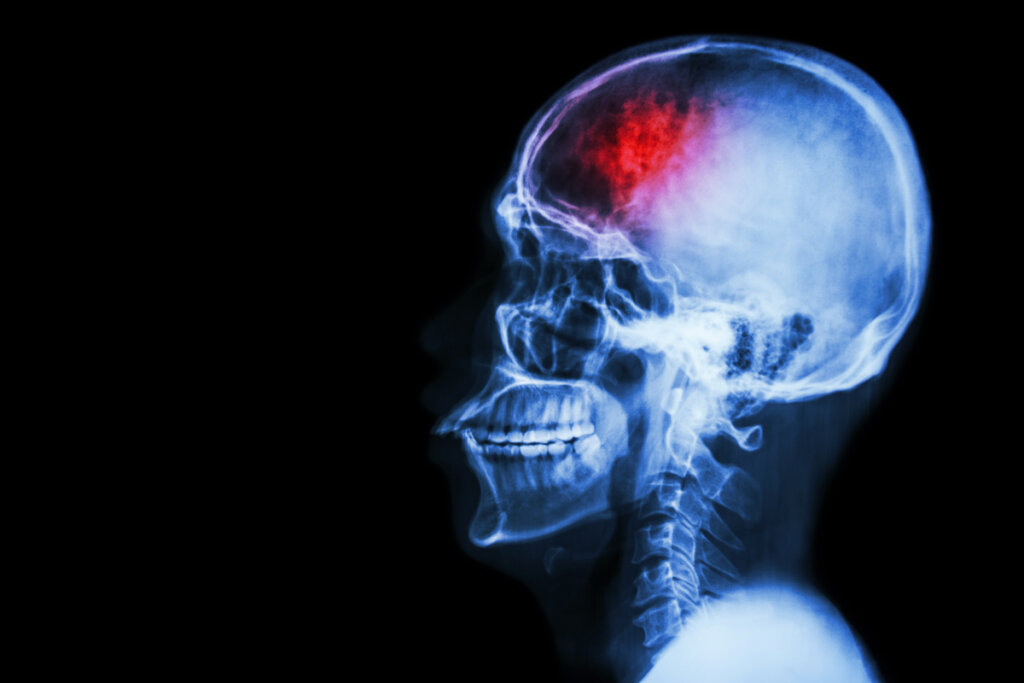

Eksekutiv dysfunksjon er ikke en lidelse i seg selv, men et underskudd som kan oppstå i forskjellige tilstander. På det nevrobiologiske nivået er eksekutiv funksjon direkte assosiert med pannelappen. Denne hjerneregionen utvikler seg først og fremst i barne- og ungdomsårene. Det er faktisk på disse stadiene at mindreårige utvikler seg og perfeksjonerer disse evnene.

Dette eksekutive underskuddet kan også vises som en del av en angstlidelse, depresjon og andre psykiatriske tilstander. Det er spesielt relevant i tilfelle av Alzheimers og andre typer demens og kompromitterer eldres autonomi og sikkerhet. På den annen side kan det også oppstå som følge av hjerneskade forårsaket av traumer eller andre skader.